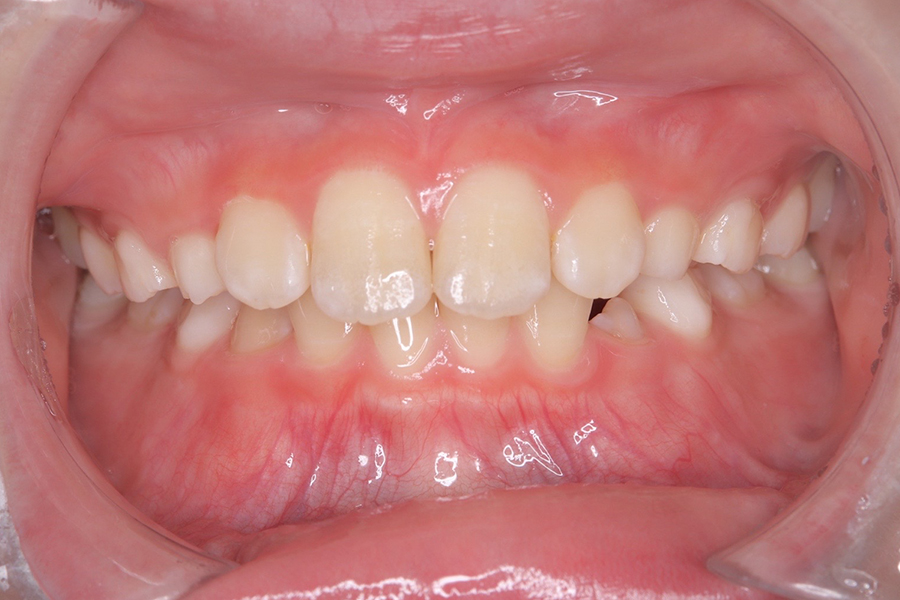

FDT症例② S.Hくん(10)

治療前

相談内容 |

うつ伏せ寝、口呼吸が気になる 歯並びの悪さ |

カウンセリング・診断結果 |

口呼吸、低位舌、上下顎劣成 |

行った治療内容 |

FDT(筋機能矯正治療/マイオブレース治療) |

治癒期間 |

2024.8.31〜 |

費用 |

385,000円(税込) |

治療リスクについて |

・お子様・保護者の協力が必要。 |

担当者からのコメント |

頑張り屋さんで真面目なHくん。正面から見ると一見綺麗ですが、横から見た時の前歯の出っ張りや永久歯の生えるスペースがないためFDTを始めました。 |